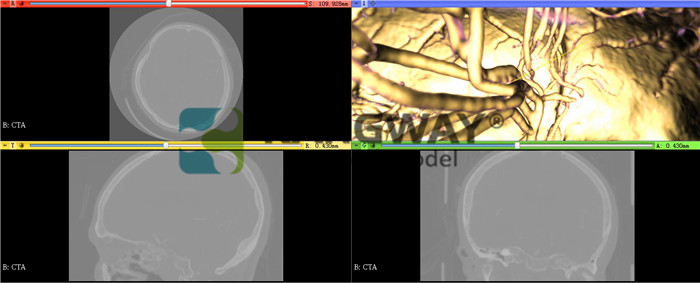

(1)支持MPR重建;

(2)支持MIP重建,可以選擇最小值,平均值和最大值進行重建;

(3)支持虛擬3D容積重建功能,支持各個方向旋轉三維圖像;

(4)支持超過20種3D重建預設;

(5)支持多平面重建,能同時顯示橫斷、冠、矢位圖像,并能夠同步調整和顯示;